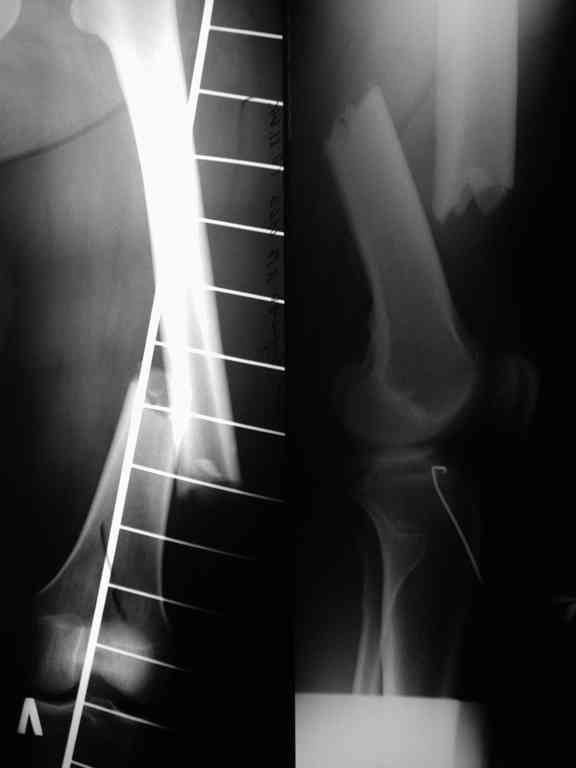

При первичном интрамедуллярном остеосинтезе применялся блокируемый гвоздь диаметром 9 мм ретроградно. У пациентки узкий костномозговой канал, поэтому были сложности (рассверливали долговато). Что касается разреза то его длина была 3-4 см не более. Т.е. насчет девитализации я согласен, но именно за счет рассверливания.

Винты с внутренней стороны кости фиксируют трансплантат, взятый из гребня подвздошной кости. Он довольно массивный и был уложен в дефект по передне-медиальной поверхности кости. тут уж пришлось действительно открываться на совесть.

В приложении рентгенограмма бедра за авгутст 2005 с согнутым гвоздем и первичные.